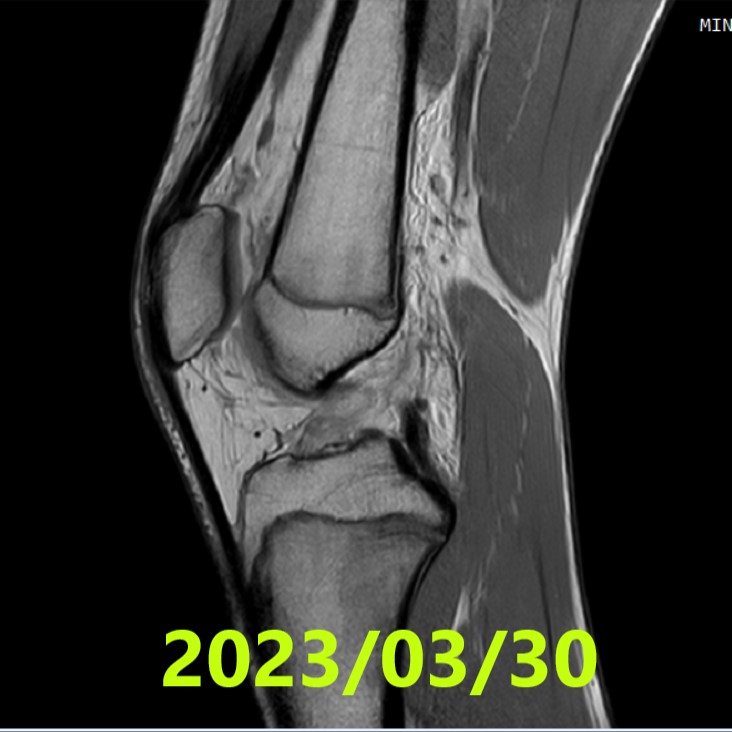

- 30 marzo 2023: RM n.1 = rottura completa del legamento crociato anteriore (LCA).

- Letture indipendenti (3 radiologi): concordi, classificazione di Ihara III (rottura con monconi dislocati).

- RM n.1 (2023/03/30): Ihara III (concorde, 3/3 lettori).